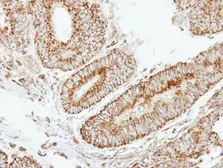

Images